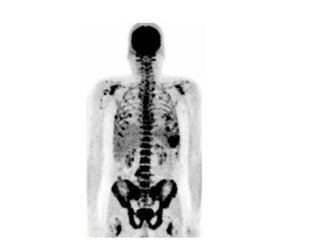

Myeloma

• Multiple myeloma is a cancer in which abnormal

cells collect in the bone marrow and form

tumors. Sometimes these abnormal cells (called

myeloma cells) collect in only one bone and form

a single tumor known as a plasmacytoma.

However, in most cases, the myeloma cells

collect in many bones, forming several tumors

and causing other problems. When this happens,

the disease is called multiple myeloma.

Myeloma • Multiple myelomais a cancer in which abnormal cells collect in the bone marrow and form tumors. Sometimes these abnormal cells (called myeloma cells) collect in only one bone and form a single tumor known as a plasmacytoma. However, in most cases, the myeloma cells collect in many bones, forming several tumors and causing other problems. When this happens, the disease is called multiple myeloma.